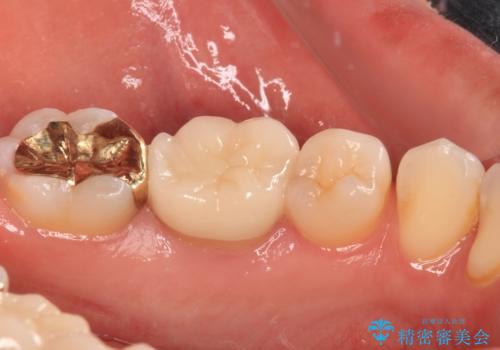

手前の歯はむし歯の範囲が広いためオールセラミッククラウンにて、最後方歯は部分的なむし歯であったのでPGAインレー(プラチナゴールドインレー)にて治療を進めることとしました。

仮詰めの状態が良くなかっただけで、むし歯が神経組織にまで及んでいることはなく、無事に治療を終えることができました。